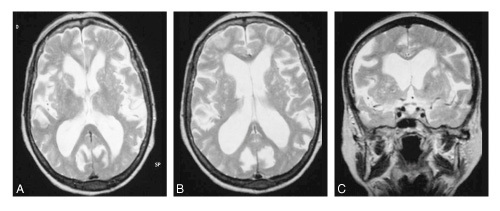

Quelle est la séquence de cette IRM? Quel diagnostic et pourquoi?

IRM séquence T2

HPN car dilatation tétra-ventriculaire, plage hyposignal T2 autour, et atrophie corticale modérée